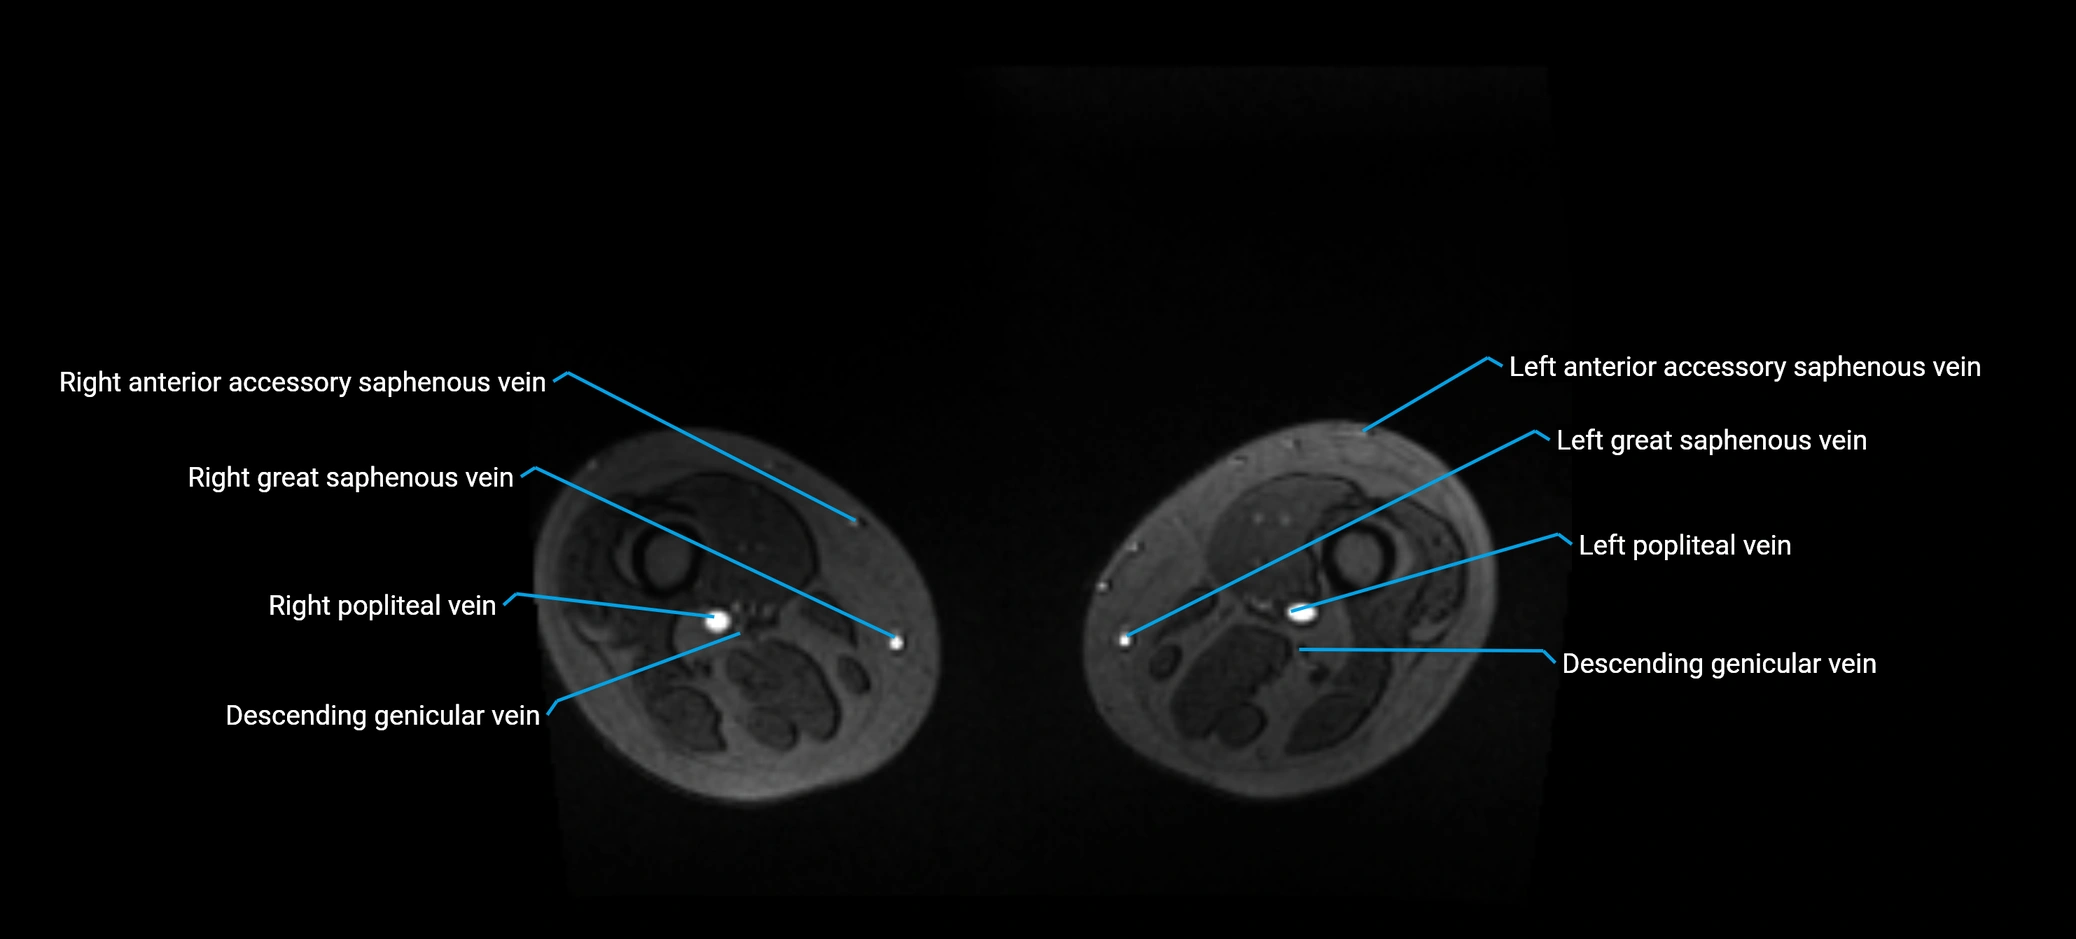

MRI image

image